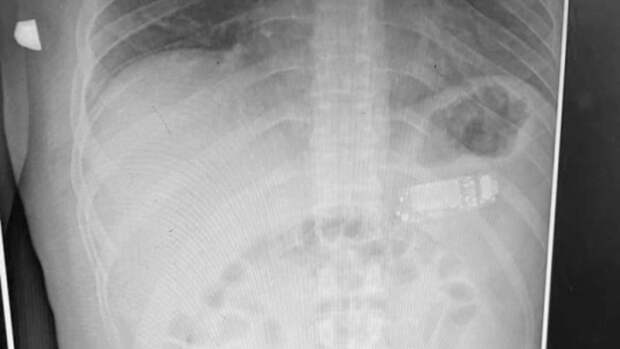

Мужчине из Косово каким-то образом удалось проглотить телефон Nokia 3310, вытащить его помогли врачи из Приштины. Об этом сообщает Metro.

В публикации отмечается, что к медикам обратился 33-летний мужчина, который пожаловался на то, что у него в животе застрял телефон. Мобильник был слишком большим, чтобы желудок смог его переварить.

Но при этом, организм мужчины подвергался опасности – из телефона могла вытечь аккумуляторная кислота.Врачам удалось вытащить телефон, разделив его на три части с помощью эндоскопии.

Руководитель медицинской бригады Скендер Теляку отметил, что осложнений после процедуры не было.